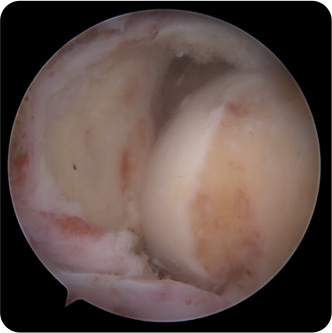

회전근개파열의 여러 모습들

기존의 삼각근을 절개하고 회전근개를 노출시켜서 수술하는 방법이 아닌 초소형 카메라인 관절내시경을 삼각근을 통과시켜 회전근개파열을 봉합합니다. 힘줄 주변의 근육 손상을 최소화시킬수 있기 때문에 수술 후 유착 반응이나 통증 반응이 감소하여 빠른 재활이 가능합니다.